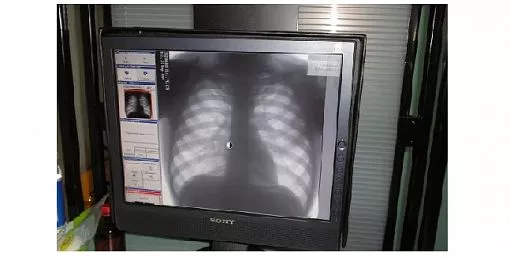

В Кировской поликлинике отремонтирован флюорограф

Администрация города Копейска сообщает: в Кировской поликлинике отремонтировали флюорографический аппарат.

Копейчане, которые по месту жительства закреплены за поликлиникой по улице Гастелло, 1а теперь смогут пройти флюорографию – с 18 января с восьми утра до 16.00.